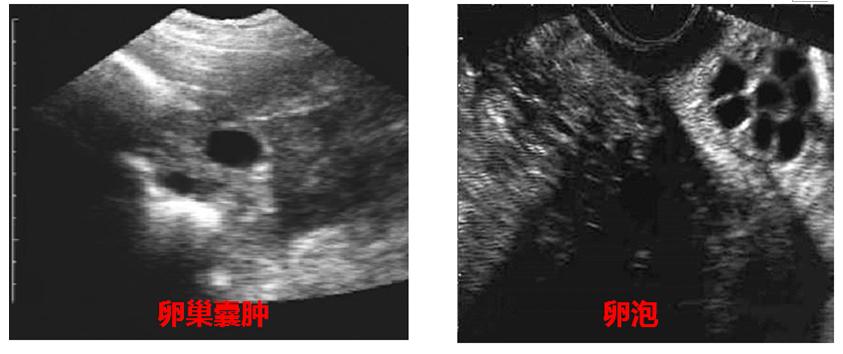

- 卵巢囊肿与卵泡

2) 妊娠检查结果会受到充盈的膀胱、子宫内的小黑点、子宫囊肿等的影响,所以要求操作人员对囊胚的形态结构特点有充分的认识;